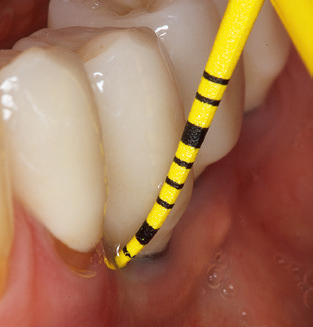

The current working concept for SPT

Fig. 4: Flexible probes with millimetre markings are recommended for the probing of dental implants (e.g. Colorvue Kit PCV11KIT6, Hu­Friedy). – Fig. 5a and b: A straight working tip (1P, W&H Dentalwerk Bürmoos GmbH) is a suitable instrument for use on all natural teeth. – Fig. 6: Curved working tips (3Pr/3Pl, W&H Dentalwerk Bürmoos GmbH) lend themselves to the processing of difficult-to-reach areas of the tooth and root surfaces (e.g. furcations). – Fig. 7: The tapered, hexagonal implant cleaning tip (1I, W&H Dentalwerk Bürmoos GmbH) permits atraumatic and efficient cleaning of the crown and abutment surfaces. – Fig. 8: Titanium and carbon curettes are suitable instruments for the manual cleaning of the implant surfaces.